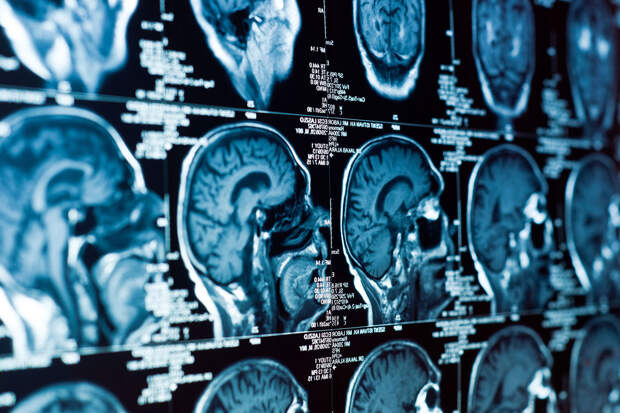

Анализ более 2600 МРТ-сканов мозга людей в возрасте от 30 до 97 лет позволил ученым проследить, как мозг трансформируется с возрастом, и как это соотносится с результатами когнитивных тестов.

Выяснилось, что изменения формы мозга происходят неравномерно: одни области сжимаются, другие — расширяются, и у людей с признаками когнитивного снижения эти искажения выражены сильнее."Мы обнаружили, что трехмерная форма мозга систематически меняется с возрастом, и эти изменения глубоко влияют на память и способность к рассуждению", — объясняет нейробиолог Нильс Янссен из Университета Ла-Лагуна.